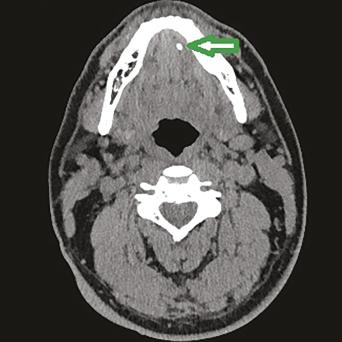

Œil rouge, blanc ou douloureux ?

En ville, le médecin généraliste est amené à voir 2 - 3 urgences ophtalmologiques par semaine. Sans matériel spécialisé, le diagnostic n’est pas toujours aisé. L'objectif de cet article est de fournir les clés pour évaluer la gravité des différents tableaux cliniques et proposer une prise en charge adaptée.